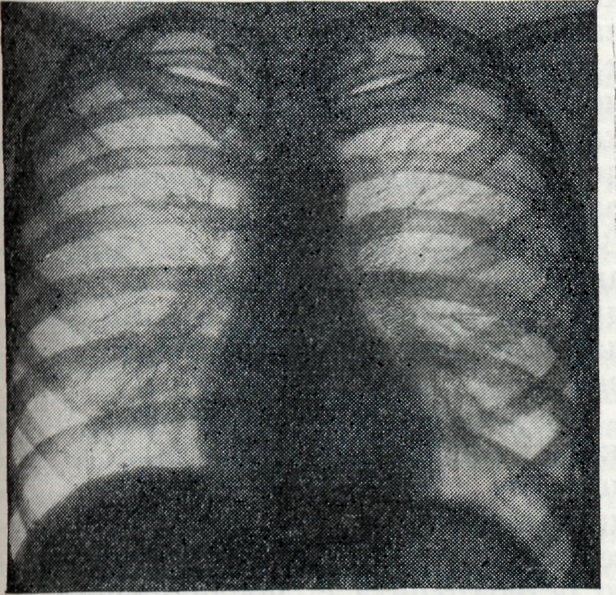

Серологические методы исследования: реакция агглютинации (Райта), реакция связывания комплемента (РСК), реакция пассивной гемагглютинации (РПГА), иммунофлюоресценции (Кунса), антитлобулиновая проба для выявления неполных антител (Кумбса) и другие. Реакция агглютинации — один из основных диагностических методов при Б. у людей и сельско-хозяйственных животных. Агглютинины, как правило, появляются в крови в ранние сроки после заражения, поэтому наибольшую диагностическую ценность реакция агглютинации представляет при острой форме Б. Помимо диагностической ценности, положительная реакция агглютинации может иметь и эпидемиологическое значение. РСК также является специфической для Б. Она появляется позже, чем реакция агглютинации, но держится дольше, что повышает её диагностическую ценность у больных хронический Б. Методика РПГА применительно к бруцеллезной инфекции разработана П. А. Вершиловой, М. И. Чернышевой с соавторами (1969). Гемагглютинирующие антитела можно обнаружить в 91—100% случаев у больных острым и подострым Б. При хронический Б. и резидуальных явлениях гемагглютинины обнаруживаются реже, однако в значительно большем проценте случаев, чем агглютинины. Зачастую гемагглютинины выявляются в тех случаях, когда все остальные реакции дают отрицательный или сомнительный результат. Специфичность и чувствительность реакции иммунофлюоресценции в динамике развития вакцинного и инфекционного процессов в условиях эксперимента, а также её диагностическая ценность у людей показана М. И. Чернышевой с соавторами (1967). В острой, подострой и хронический форме инфекции реакция иммунофлюоресценции выявляет антитела в сыворотке в несколько большем проценте случаев, чем реакция агглютинации. Высокая чувствительность пробы Кумбса при Б. доказана как у больных, так и у людей, находящихся в контакте с инфицированным материалом или животными, а также у лиц, проживающих в районах, неблагополучных по Б. крупного и мелкого рогатого скота. Аитиглобулиновая проба Кумбса рекомендуется в качестве диагностического метода при хронический и латентных формах Б. Пробу Кумбса можно применять для углублённого обследования людей и животных в целях ретроспективного выявления контакта с антигеном, а также изучения иммунологической структуры населения в очагах инфекции. Общепринятым методом ускоренной диагностики Б. у человека является пластинчатая реакция агглютинации Хаддлсона. В основе её лежит использование цельной сыворотки и антигена в концентрированном виде. Реакция специфична, становится положительной в раннем периоде заболевания и держится довольно долго. Преимущество пластинчатой реакции агглютинации по сравнению с пробирочной заключается в том, что постановка первой доступна в любой лаборатории и результат получается быстро. В процессе развития бруцеллезной инфекции у больных наблюдается повышение опсонической способности крови. В 1933 г. Хаддлсон, Джонсон и Хаманн (I. F. Huddleson, Н. W. Johnson, E. E. Hamann) предложили пробу для диагностики бруцеллеза — опсонофагоцитарную реакцию. Она основана на способности сегментированных нейтрофилов фагоцитировать бруцеллы благодаря наличию в крови человека специфических опсонинов, нарастающих в процессе бруцеллезной инфекции. Относительно высокий фагоцитоз наблюдается у лиц, не болевших, но соприкасавшихся с возбудителем заболевания, а также у вакцинированных живой вакциной. Реакция вполне специфична и чувствительна, однако она не отражает количества опсонинов в крови. Виктор (J. Victor) с соавторами (1952) предложили метод установления титров опсонинов в сыворотке крови. Все большее значение приобретает изучение состава сывороточных иммуноглобулинов в различные фазы бруцеллезной инфекции. В ранние сроки после заражения появляются антитела относящиеся к макроглобулинам (IgM). Микроглобулины (IgG) обычно выявляются в более поздние сроки. Определение иммуноглобулинов с помощью цистеиновой пробы приобретает диагностическое и прогностическое значение, а также способствует выбору рациональных методов лечения и более объективной оценке его эффективности. Проба Бюрне основана на способности организма, сенсибилизированного бруцеллезным аллергеном, специфически отвечать местной реакцией на внутрикожное введение небольших количеств аллергена (бруцеллина). Проба, как правило, становится положительной в 70—85% случаев к концу первого месяца заболевания, но бывают случаи и более раннего появления её (7—8-й день болезни). Реакция сохраняется очень долго, иногда годами. В отдельных случаях кожная проба может быть положительной и у клинически здоровых людей. В таких случаях она свидетельствует об аллергической перестройке организма под влиянием контакта с бруцеллезным антигеном, что нередко наблюдается у лиц, которые обслуживают больной Б. крупный рогатый скот. Кожная проба становится положительной и после вакцинации людей живой бруцеллезной вакциной. Серологические реакции и аллергическая кожная проба по своему диагностическому значению не равноценны, вследствие чего не могут заменить друг друга. Это обусловливает необходимость применения комплексного сероаллергического метода, являющегося наиболее надёжным способом диагностики Б. Смотри также Гемагглютинация, Иммунофлюоресценция, Кумбса реакция, Райта реакция, . Хаддисона реакция. Рентгенологическое исследование при Б. ранее ограничивалось главным образом изучением состояния опорно-двигательного аппарата, а следовательно, выявлением изменений в суставах, периартикулярных тканях, реже губчатых и трубчатых костях. Однако широкое применение рентгенологического исследования больных Б. показало, что и в фазах генерализации инфекции, и в латентном периоде встречаются также бруцеллезный внутригрудной лимфаденит (рисунок 5 и 6), бронхопневмонии и плевриты бруцеллезного происхождения. Лимфаденит при Б. проявляется рентгенологически в виде гиперплазии лимф, узлов корней лёгких, нередко с прикорневой инфильтрацией тяжистого или диффузного характера. Наблюдается как двустороннее, так и одностороннее поражение. В клинико-рентгенологическом аспекте следует иметь в виду быстрое возникновение, но очень медленное обратное развитие подобных изменений, что, впрочем, относится ко всем изменениям в лёгких при Б. В отличие от таких заболеваний, как саркоидоз, увеличение лимф. узлов при Б. не даёт картины резких полициклических бугристостей, прикорневая инфильтрация в начале процесса носит диффузный характер, свойственный скорее прикорневой инфильтрации при туберкулёзе, чем при болезни Бека. Признаки бронхостеноза при этом отсутствуют. Дифференциальная диагностика с лимфогранулематозом и ретикулосаркоматозом на основании одних лишь рентгенологических данных затруднительна и должна базироваться на картине крови, реакциях Райта, Хаддлсона и Бюрне.

Бронхопневмонии бруцеллезной этиологии также чаще всего обусловливают инфильтраты, связанные с корнем лёгкого, гл. обр. с хвостовой его частью. По рентгенологическим признакам их трудно отличить от бронхопневмоний, вызванных банальной флорой, в связи с чем необходимо учитывать общую картину заболевания, в частности наличие характерных для Б. периферических полиаденитов, фиброзитов, артритов, периартритов и т. д. Этими же соображениями следует руководствоваться при дифференциальной диагностике бруцеллезных плевритов.

Острые и хронический гематогенные диссеминации в лёгочной ткани также описаны при Б., хотя встречаются значительно реже, чем лимфадениты и бронхопневмонии. Гематогенные очаги Б. в лёгких мало отличаются от метастазов рака и гематогенного туберкулёза. Против туберкулёза говорит одновременное увеличение лимф, узлов корней лёгких, однако оно не обязательно. Положительные специфические реакции на Б. и отрицательные данные анализов мокроты и кожных проб на туберкулёз в сочетании с клиническим течением являются при гематогенно-диссеминированных формах Б. лёгких основными в установлении диагноза. То же следует учитывать в дифференциальной диагностике с метастазами рака и других злокачественных опухолей. Артралгии, часто сопровождающие стадию генерализации Б., как правило, рентгенологически бессимптомны, что, впрочем, также имеет важное значение в дифференциальной диагностике с полиартритами иного происхождения, в частности с ревматоидным полиартритом, при котором, как правило, относительно рано наблюдается остеопороз. Хорошо выявляемые клинически типичные для Б. периартриты, фиброзиты и поражения слизистых периартикулярных сумок в остром периоде Б. рентгенологически бессимптомны, но становятся рентгенопозитивными в фазе обызвесвления. Наиболее часты при Б. — подострые и хронический синовиты. Их преимущественная локализация — коленные, локтевые, голеностопные, реже лучезапястные и тазобедренные суставы. При этом виде поражений рентгенограммы обычно не дают указаний на деструктивные изменения, а пункция сустава — на присутствие бруцелл. Бурситы рентгенологически дают лишь картину умеренного локального остеопороза и увеличения объёма мягких тканей. В таких суставах, как коленные, выявляется понижение прозрачности хорошо видимых в норме заворотов сумки. Т. о., бруцеллезный бурсит на основании одной лишь рентгенологической картины не отличим от ревматического поражения и начальной фазы ревматоидного полиартрита. В отличие от описанных выше синовитов, истинные остеоартриты при Б. наблюдаются значительно реже и являются результатом формирования локального очага в костно-суставном аппарате, чаще всего в под-острой и хронически-рецидивной фазе заболевания.